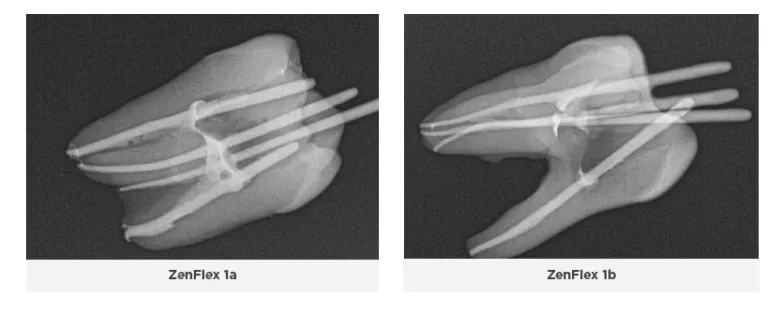

ZenFlex files are nickel-titanium files that have undergone a patented heat treatment to provide them with a blend of flexibility and strength not typically seen in a file with this small mass. These files are designed to be as resistant or more resistant to torsional stresses relative to major rotary file competitors despite having a smaller maximum flute diameter and smaller mass. Two unique features that differentiate ZenFlex files from ProTaper Gold and ProTaper Next files are their controlled memory and maximum flute diameter of 1mm. ZenFlex files undergo a proprietary heat treatment process that improves their strength and resistance to cyclic fatigue, torsional stress and separation, as well as making them significantly more flexible and able to retain their cutting efficiency by preserving their sharp cutting edge. Unlike other manufacturers, Kerr uses a proprietary double heat treatment process. The files are heat treated first, their shape is then ground into them, and then they undergo a second heat treatment to make them stronger and sharper. They also heat treat each file differently based on its mass, therefore the optimum qualities for each file are obtained: smaller more flexible files become stronger, and larger stronger files become more flexible. The files come in both 0.04 and 0.06 tapers, have a non-end cutting tip, and are extremely strong and flexible with controlled memory. Their controlled memory and 1mm maximum flute diameter enable them to follow the natural contour of the canal and be minimally invasive to successfully instrument the canal without removing too much dentin from the coronal and middle thirds and thus preserve the integrity of the tooth structure. ZenFlex files have a centered mass of rotation with a triangular cross-section to provide excellent cutting and debris removal with little to no apical debris extrusion.

It was immediately observed that the 0.04 tapered ZenFlex files used in this comparison trial cut much more efficiently and allow the clinician to treat the tooth in a more dynamic and flexible workflow if one chooses to do so. Therefore, the clinician can use his or her preferred workflow and technique to instrument the canal.

Moreover, the time to treat each tooth was 30-50% faster than the ProTaper Gold and Next and file systems because the ZenFlex files cut more efficiently. Noticeably less binding and rotational force was applied to the tooth when using the ZenFlex files. Hardly any apical extrusion of debris was noted, and debris was observed to be removed coronally. The natural anatomy of the canals was preserved, and no evidence of transportation, ledging, nor blocking of any of the canals was observed.

In situations when the canals are constricted and stenotic, a lot of filing must typically be performed to establish a glide-path to working length before a rotary file can be taken to length(10,11,12,10). However, the ZenFlex files cut so well that, along with their flexibility and controlled memory, clinicians can negotiate these types of scenarios quickly using ZenFlex files in conjunction with the Traverse Orifice Opener and Glide Path files, difficult cases take much less time and can be performed more efficiently without destroying the anatomy of the tooth or separating files.

The Medium Fine (MF) 0.04 taper Kerr AutoFit Greater Taper gutta-percha was used with the 0.04 taper ZenFlex files, and had to be trimmed to the corresponding master apical file size. Once fitted and trimmed, there were no issues seating the gutta-percha to the established working length. Should a clinician use the 0.06 taper ZenFlex files, the AutoFit Greater Taper gutta-percha is also available in a 0.06 taper to match.

Two dimensional radiographs were taken of the teeth after endodontic therapy was completed and reviewed. In some of the ProTaper Gold and Next cases, working length was not reached radiographically, even though it was thought to be achieved clinically. As an electronic apex locator cannot be used to assess working length on extracted teeth, working length was established with visual observation. Clinically, an electronic apex locator would have been used, and adjustments would have been made throughout the entire process to ensure the working length was reached. The teeth were selected at random, and some of the orifices and canals were calcified or stenotic. In a live clinical scenario, ultrasonics would have been used to negotiate these constrictions more easily; however that being said, the ZenFlex and Traverse file systems allowed these canals to be negotiated and treated without issue. Additionally, the teeth treated with the ZenFlex files appeared to have the best preservation of the natural shape of the canal and conserved the most tooth structure. This was not the case with the ProTaper Gold and Next file systems. Less efficient cutting with more aggressive removal of tooth structure was noted, resulting in a loss in the original anatomy of the canals. ZenFlex is an ideal file that balances strength and flexibility to allow clinicians to reach the working length while being minimally invasive, even in cases with complex canal anatomies.